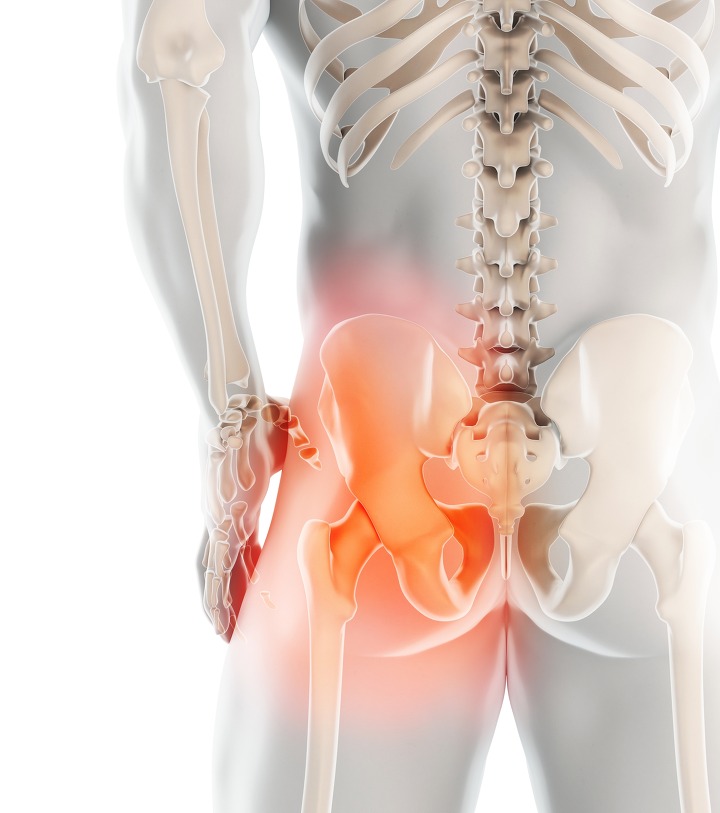

고관절이란?

고관절 통증 증상(엉덩관절)은 오른쪽과 왼쪽의 골반과 넙다리뼈가 연결된 관절의 통증을 일컫습니다. 고관절은 상체의 하중을 분산시키는 역할을 하며, 일어서거나 앉거나 일상생활에서 자주 쓰이는 관절이며 부담도 잘 받게 됩니다. 모양도 크기도 탁구공만 합니다. 일상적으로 걸을 때 고관절에 체중의 3~4.5배의 무게가 실리게 됩니다. 계단을 오를 때는 대퇴골두에 전해지는 무게는 몸무게의 8배, 달리는 경우 10배에 가까운 하중을 견뎌내애 한다고 합니다. 탁구공 크기만 한 대퇴골두가 감당하기에는 너무 무겁기 때문에 고관절이 느끼는 부담도 크고 쉽게 손상될 수 있습니다. 다른 관절과 마찬가지로 감당하기 어려운 충격이나 무게가 가해지면 고관절 통증 증상이 발생하게 되는데요. 퇴행성 고관절염, 대퇴골 골절, 대퇴골두 무혈성 괴사, 선천성 고관절 탈구 등이 대표적인 고관절 통증 질환입니다.